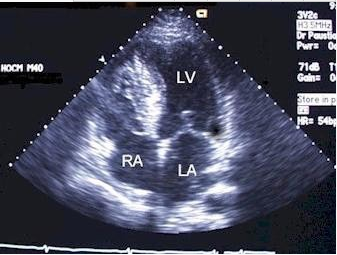

查看答案如图三尖瓣病例最可能的诊断

A、右室双腔

B、三尖瓣缺如

C、异位腱索

D、三尖瓣下移

E、室间隔缺损

查看答案